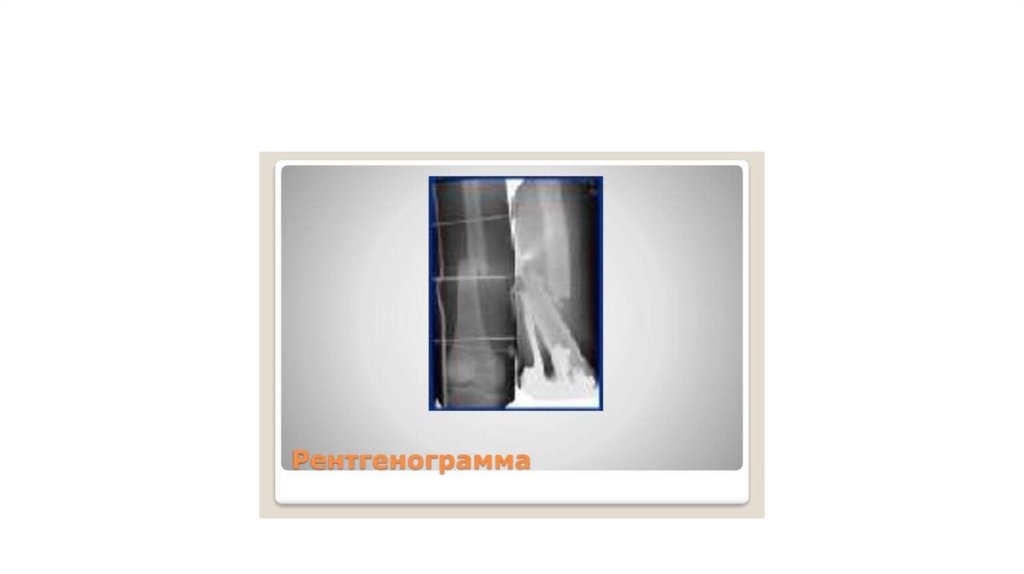

ПЕРЕЛОМЫ ДИАФИЗА

БЕДРЕННОЙ КОСТИ